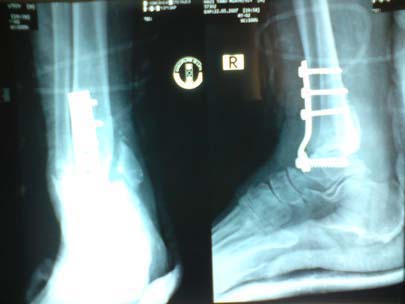

History of trivial injury to the foot, clinical picture and investigations were considered compatible with Charcot arthropathy of the ankle and foot. As his right ankle was grossly unstable, he was treated with ankle arthrodesis (Fig.2). A ‘T’ shaped plate and five screws were used for arthrodesis of the ankle and immobilised with a sort leg plaster cast. His ankle fused over the next eight months. As a result, he could walk pain free but with some difficulty.

Fig. 2. Post-operative X-ray: Ankle arthrodesis with plate and screws